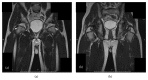

Traumatic dislocation of the hip in a child caused by trivial force for age

Traumatic hip dislocation in children has a relatively rare occurrence. There are some residual complications, such as avascular necrosis of the femoral head, growth disturbance caused by premature fusion, neurological injury, recurrent dislocation, and posttraumatic arthritis. There is no consensus in the literature about the period of non-weight bearing after reduction. A rare case of a 13-year-old boy of hip dislocation caused by trivial force for age is reported followed by review of the pediatric literatures with treatment recommendation.